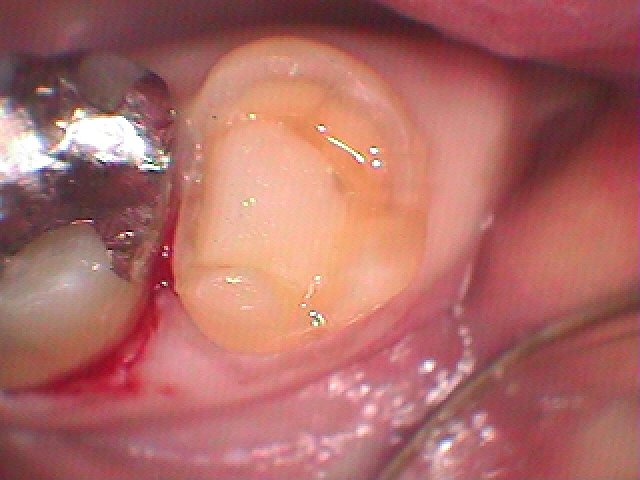

銀歯を外していきました

悪いところを除去してCR樹脂にて覆罩を行っています